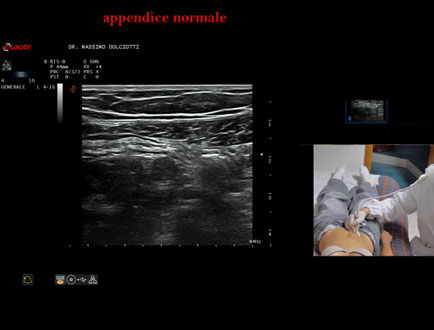

Data inserimento: 01/08/2025

Ecografia del: 11/07/2025

Strumento: Esaote MyLab Eight

Sonda: Lineare Multifrequenza 4-15 MHz

Età Paziente: M 12 anni

Motivazione dell'esame: recente infezione virus mononucleosi infettiva

Commento all'esame: le immagini ed il video documentano l'appendice di calibro regolare (4,8-5,2 mm - v.n. < 6 mm).

Conclusioni: appendice normale (normal appendix).

Presentazione: Dr. Massimo Dolciotti - Ancona